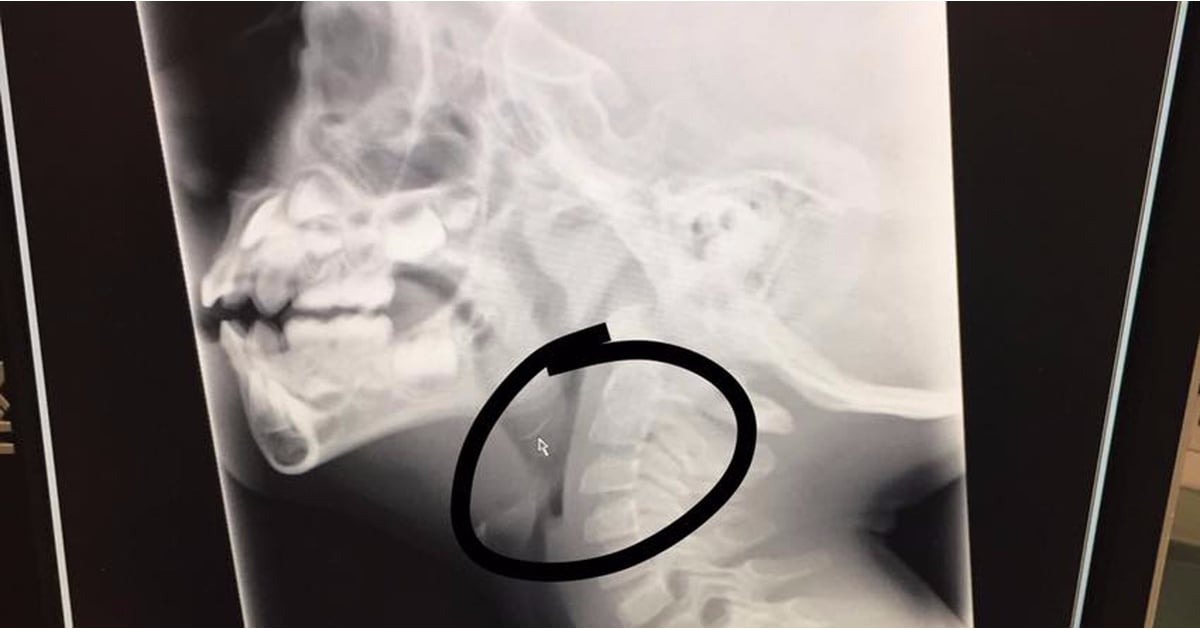

Grill Wire Brush Danger . Wire brushes can scratch and damage delicate grill surfaces, especially those made of. wire grill brushes used to clean cooking surfaces can pose a surprising risk when bristles come loose. wire grill brushes are dangerous because the wires can snap off. here's what you need to know about the dangers of wire grill brushes and whether experts recommend you use. are wire grill brushes dangerous? Expert warns about injuries caused by metal bristles which end up in food and become lodged in the mouth,. toby amidor, ms, rd, cdn, fand, nutrition expert and author of the family immunity cookbook, confirms that wire grill cleaning brushes can lose bristles that can get lodged in your food and. It's unlikely, but if you use a wire brush to clean your grill, these. damage to grill surfaces: Consumer reports reveals how you can avoid wire grill brush dangers.

damage to grill surfaces: Consumer reports reveals how you can avoid wire grill brush dangers. toby amidor, ms, rd, cdn, fand, nutrition expert and author of the family immunity cookbook, confirms that wire grill cleaning brushes can lose bristles that can get lodged in your food and. are wire grill brushes dangerous? here's what you need to know about the dangers of wire grill brushes and whether experts recommend you use. wire grill brushes are dangerous because the wires can snap off. It's unlikely, but if you use a wire brush to clean your grill, these. Wire brushes can scratch and damage delicate grill surfaces, especially those made of. wire grill brushes used to clean cooking surfaces can pose a surprising risk when bristles come loose. Expert warns about injuries caused by metal bristles which end up in food and become lodged in the mouth,.

Grill Wire Brush Danger damage to grill surfaces: Expert warns about injuries caused by metal bristles which end up in food and become lodged in the mouth,. Consumer reports reveals how you can avoid wire grill brush dangers. are wire grill brushes dangerous? wire grill brushes used to clean cooking surfaces can pose a surprising risk when bristles come loose. wire grill brushes are dangerous because the wires can snap off. Wire brushes can scratch and damage delicate grill surfaces, especially those made of. damage to grill surfaces: toby amidor, ms, rd, cdn, fand, nutrition expert and author of the family immunity cookbook, confirms that wire grill cleaning brushes can lose bristles that can get lodged in your food and. It's unlikely, but if you use a wire brush to clean your grill, these. here's what you need to know about the dangers of wire grill brushes and whether experts recommend you use.